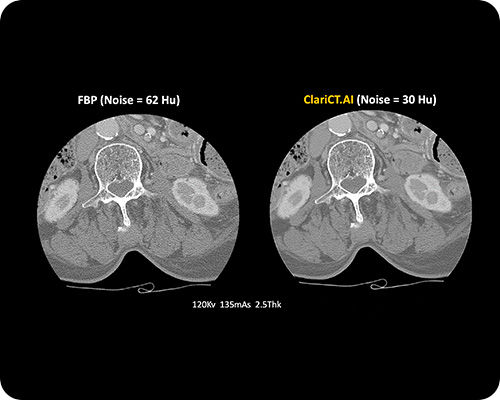

ClariCT.AI

AI-Powered Radiation Reduction

The first AI software that dramatically reduces radiation exposure while delivering the highest quality CT images using advanced AI denoising technology.

Reduces radiation exposure by 70-95% while maintaining superior image quality